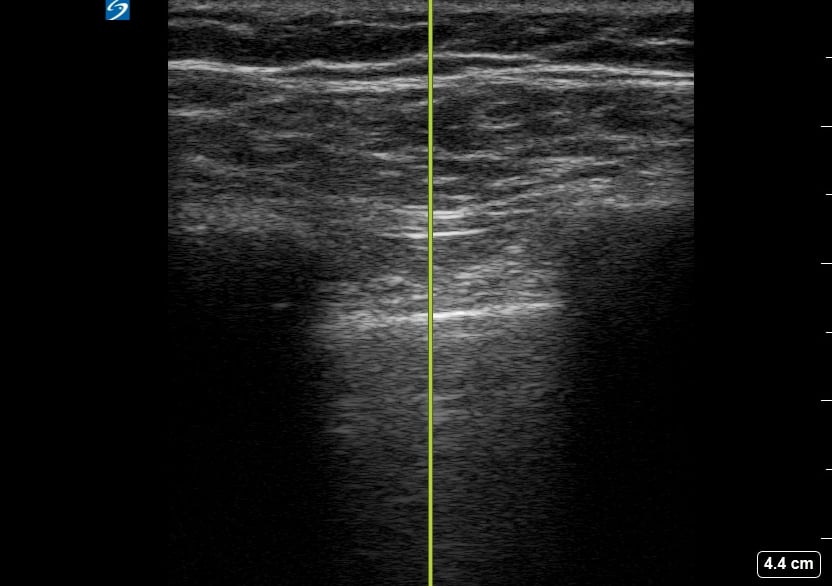

Pneumothorax

A pneumothorax, or collapsed lung, occurs when air leaks into the space between the lung and chest wall, causing the lung to partially or completely deflate. In a medical setting, prompt diagnosis is crucial to prevent respiratory distress. Ultrasound is a valuable tool for quick assessment, revealing characteristic signs like the absence of lung sliding or the presence of a “barcode” or “stratosphere” sign in M-mode, aiding rapid clinical decisions.

Ultrasound imaging for pneumothorax offers a non-invasive, real-time method for detection, especially in emergency and critical care. Key ultrasound findings guide clinicians in identifying this potentially life-threatening condition, facilitating timely intervention and improved patient outcomes. Understanding these signs is essential for medical professionals utilizing point-of-care ultrasound for lung pathology.